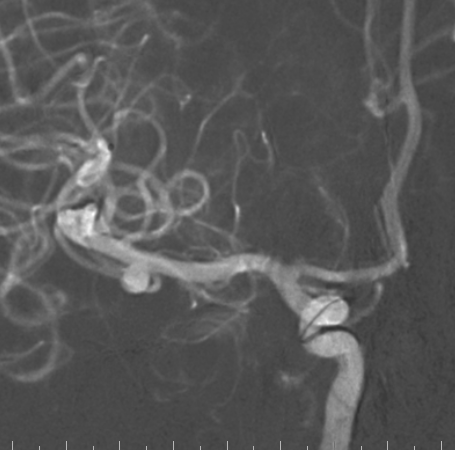

脑血管造影

右侧颈总造影:右侧大脑中动脉瘤

右侧大脑中动脉瘤,瘤颈处发出颞支,颈宽3.79mm,瘤高3.51mm,远近端载瘤动脉直径分别为2.43mm、2.52mm。